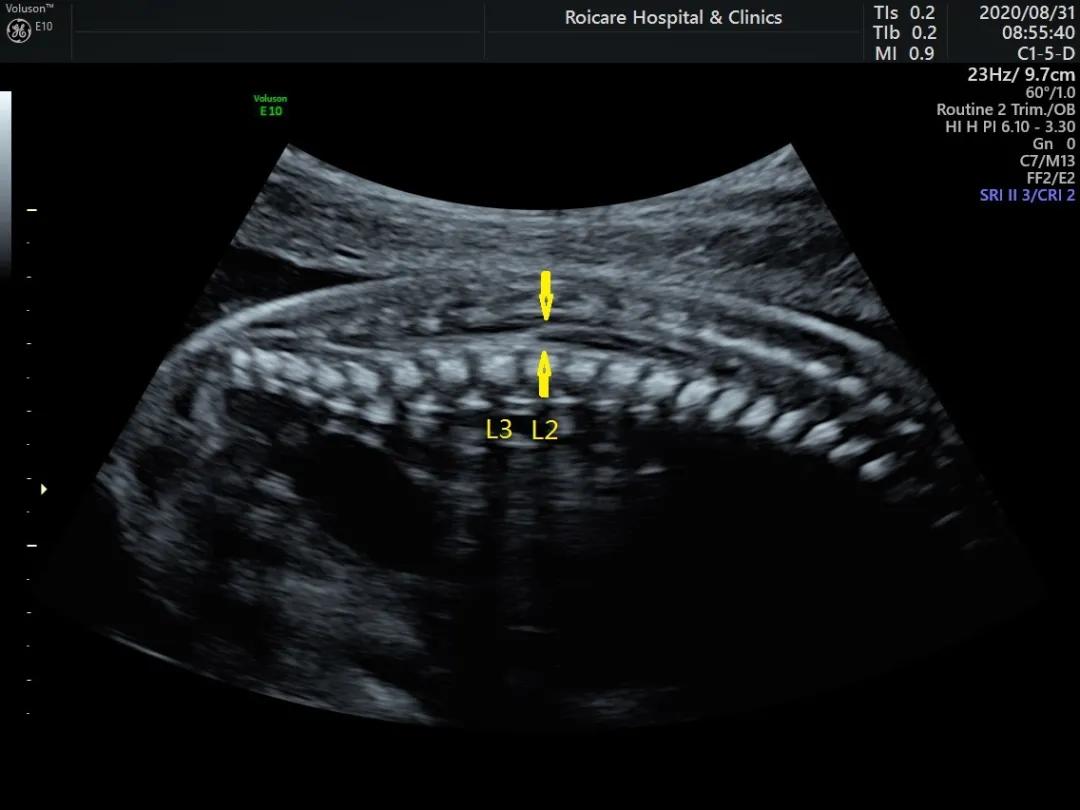

正常位置的脊髓圆锥

出生时脊髓圆锥位于第2腰椎(L2)至第3腰椎(L3)水平,出生后3个月位于L1~L2水平,与成人相同。脊髓下端因各种先天或后天原因受制于椎管的末端不能正常上升,使其位置低于正常,由此而导致的一系列临床神经功能障碍和畸形的综合征即称为脊髓拴系综合征。